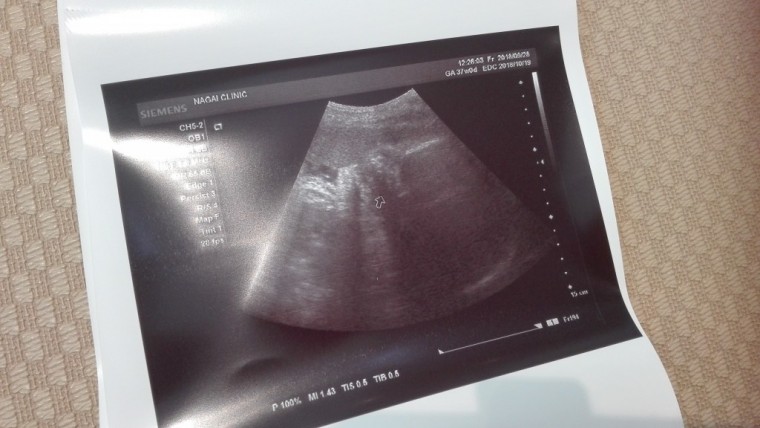

妊娠10ヶ月 妊娠36週,37週,38週,39週(妊娠後期)の超音波写真 妊娠10ヶ月

妊娠10ヶ月の超音波写真

37週のエコー写真☆ ちょうどお口をムニャムニャ動かしてる所で可愛かったです。

妊娠10ヶ月(37週0日)撮影日:2018年9月28日